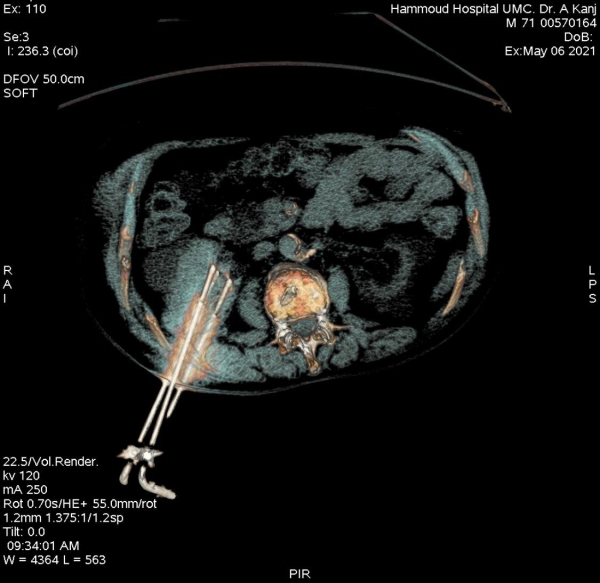

إنجاز طبي جديد في مستشفى حمود الجامعي لأول مرة في الجنوب، عبارة عن علاج ورم ضخم في الكلية مكون من كتلة سرطانية تتخطى ال٦ سنتم بالتقنية الحديثة Cryoablation Of Tumor Under CT

وهي تقنية تجميد وقتل الأورام السرطانية الخبيثة دون إجراء عملية جراحية ودون آلام.

قام بإجراء العملية الدكتورعلي كنج، رئيس قسم الأشعة في مستشفى حمود الجامعي، لمريض في العقد السادس من عمره من خلال تخدير موضعي حيث تمكن المريض من مغادرة المستشفى في اليوم الثاني. بعد نجاح العملية، أكد الدكتور كنج على أهمية هذه التقنية في علاج الأمراض السرطانية المختلفة كعلاج أساسي، أو كعلاج مساعد للعلاج الطبي وللتخلص من الآلام الناتجة من الأمراض السرطانية.